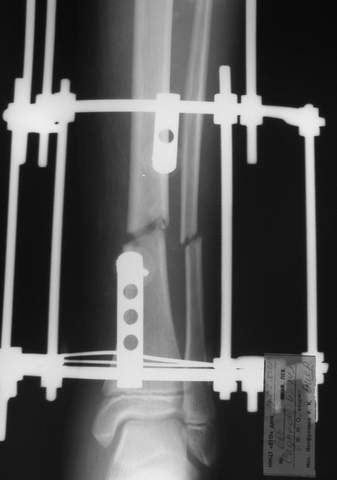

3b

3c

В аттачте № 3 - один из примеров полукольцевого аппарат...

Это уже я баловался.

Итог? Работы больше (по времени и

интраоп "подгонке"), срастается также, а особого преимущества по сравнению с

"чиста" кольцевым (вес, удобство ношения и пр.) - я, по крайней мере,

не нашел.

Теперь не балуюсь.